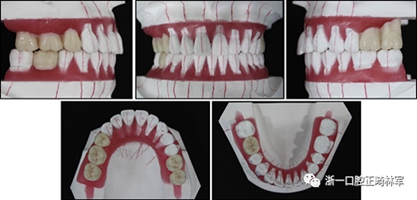

完成診斷性設(shè)計后,治療后穩(wěn)定的咬合是確定的(圖5)。進行治療之前,治療計劃和順序需要通過涉及正畸,牙周病和修復(fù)的多學(xué)科綜合治療方法加以確認(圖6)。牙周治療應(yīng)在正畸治療前完成。牙周疾病的治療采用全口潔治,上頜和下頜前牙區(qū)的刮治術(shù),以及下頜左側(cè)后牙區(qū)的翻瓣手術(shù)。休息3個月后,幾乎每個部位都實現(xiàn)了牙周袋深度縮小,探針出血幾乎沒有(表III)??刂蒲装Y后,開始正畸治療。在正畸治療期間定期進行牙周維護的復(fù)診檢查。

圖5. 治療計劃的診斷性設(shè)置

圖6. 治療計劃和應(yīng)用正畸學(xué),牙周學(xué)和修復(fù)學(xué)的跨學(xué)科綜合治療順序

拔除下頜左側(cè)側(cè)切牙,除了4顆前牙外,下頜和上頜牙齒通過0.022英寸的Clippy-C裝置(日本東京的Tomy)粘接聯(lián)合。磨牙管粘結(jié)在下頜磨牙上。排齊過程從0.014英寸的鎳鈦弓絲開始,然后是0.016英寸的鎳鈦弓絲。為了美觀,在拔除的下頜左側(cè)側(cè)切牙間隙中放入一個修復(fù)體。為了防止牙齒的圓形轉(zhuǎn)動,4根上頜前牙被繞過,使牙齒能在尖牙被推向遠中后排齊。將兩個TADs(Orlus,Ortholution,Seoul,Korea)放置在腭板,并且有鉤子附著。將一小段0.016英寸的不銹鋼弓絲放置在上頜左側(cè)尖牙和前磨牙上,并且通過附著在腭板上的鉤子將上頜尖牙和左側(cè)前磨牙推向遠中。

對于近中傾斜和過度萌出的上頜右側(cè)尖牙,需要控制牙齒向遠中傾斜和向下推入。用兩個鉤子在兩側(cè)施加不同方向的力,以期望右側(cè)尖牙的推入(圖7)。在上頜尖牙遠中移動后,用一根0.014英寸的鎳鈦弓絲將4顆上頜前牙排齊。放置逐漸變硬的弓絲,直到上下兩個牙弓都放置0.017*0.025英寸的不銹鋼弓絲。然后關(guān)閉下頜前牙區(qū)間隙,用完全相同的力學(xué)原理將上頜全牙列向遠中移動,以獲得適當(dāng)?shù)母埠虾透采w。此外,還有一個0.017*0.025英寸β-鈦絲的直立彈簧應(yīng)用于下頜右側(cè)第二磨牙。當(dāng)直立彈簧接合到主弓絲上時,引起前磨牙的推入,第二磨牙的推出,前磨牙的頰側(cè)傾斜以及第二磨牙的舌側(cè)傾斜,以矯正牙弓形態(tài)(圖8)。